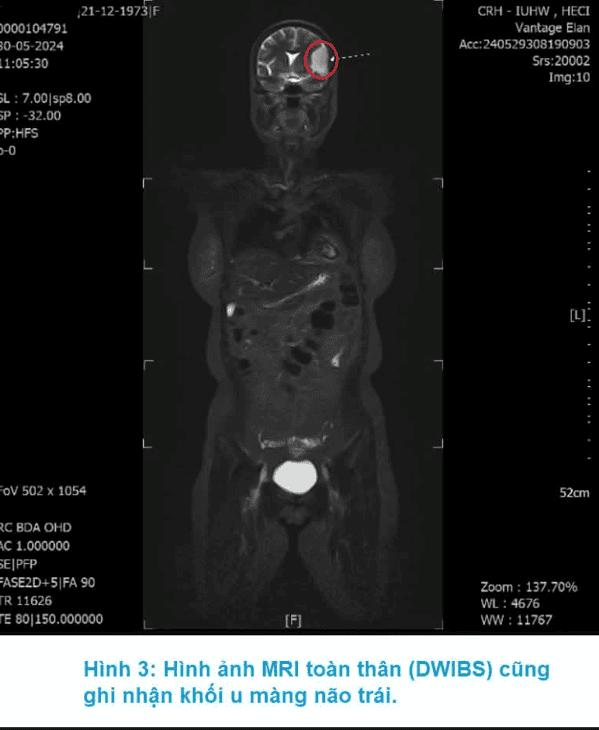

MRI DWIBS (Diffusion-weighted Whole Body Imaging with Background Suppression) là kỹ thuật chụp cộng hưởng từ khuếch tán toàn thân xóa nền, cho phép tầm soát toàn bộ cơ thể trong một lần chụp. Phương pháp này được ứng dụng hiệu quả trong tầm soát ung thư, phát hiện di căn và theo dõi tiến triển bệnh. So với các phương pháp chẩn đoán hình ảnh khác, MRI DWIBS sở hữu nhiều ưu điểm như: không nhiễm xạ, không cần tiêm thuốc cản quang, thời gian chụp toàn thân rất kỹ từ 50đến60 phút, người bệnh có thể sinh hoạt bình thường ngay sau khi thực hiện và phù hợp với cả người mắc bệnh đái tháo đường. Tuy nhiên, một số trường hợp không được chỉ định chụp MRI DWIBS, bao gồm người đang mang máy tạo nhịp tim, có mảnh đạn, mảnh kim loại gần mạch máu lớn hoặc các cấu trúc nguy hiểm, các dụng cụ cấy ghép trong cơ thể… Những trường hợp này cần thông báo đầy đủ với bác sĩ trước khi thực hiện chụp chiếu.